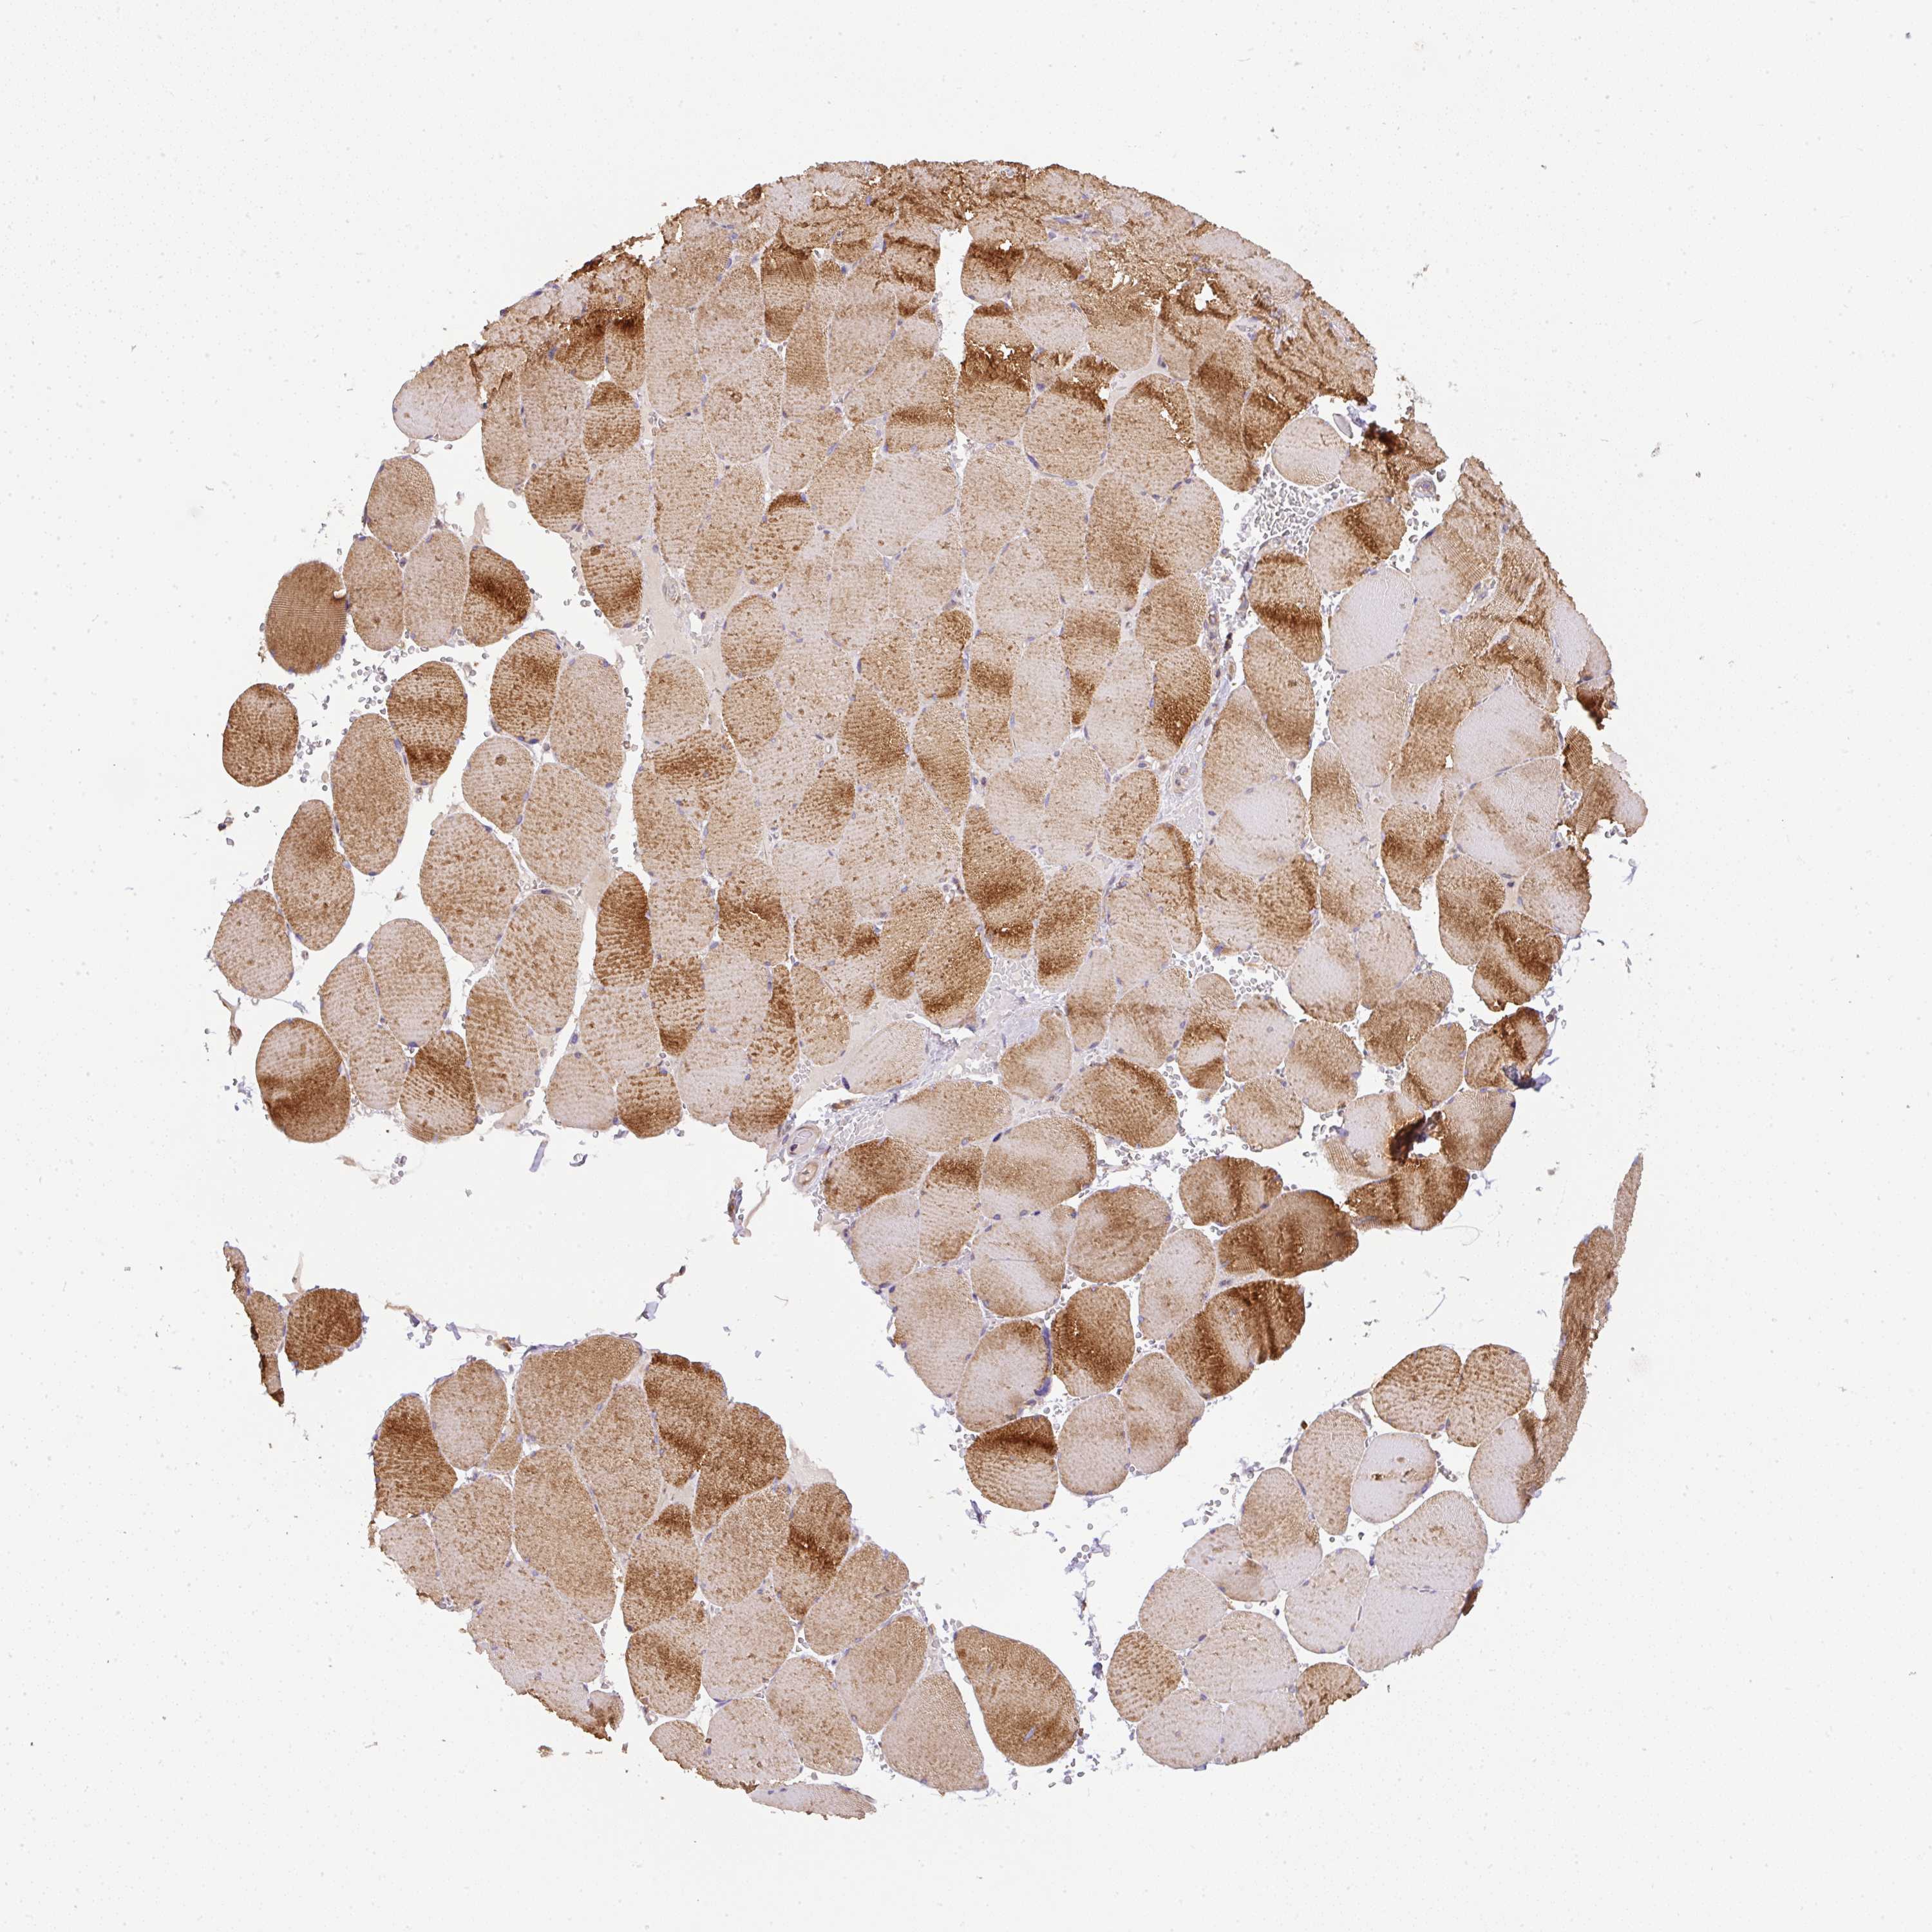

TISSUE PRIMARY DATA SKELETAL MUSCLE Show tissue menu

SKELETAL MUSCLE - Antibody stainingi

Antibody staining in the annotated cell types in the current human tissue is reported as not detected, low, medium, or high, based on conventional immunohistochemistry profiling in selected tissues. This score is based on the combination of the staining intensity and fraction of stained cells.

Each image is clickable and will lead to virtual microscopy that enables deeper exploration of all samples and also displays staining intensity scores, fraction scores and subcellular localization as well as patient and tissue information for each sample.

Antibody HPA040472Antibody HPA048436Antibody CAB037302

Myocytes HighHighNot detected